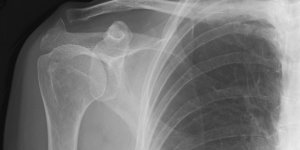

Lung Cancer | Pancoast

Published on Feb 16, 2021

71 male First appointment 3 Month history of Right rhomboid pain. Aggravated by shoulder movements. Struggles to get to sleep and occasionally wakes up. No P+N or numbness. No dizziness, diplopia, dysarthria, dysphagia, drop attacks, nausea. Exam Slight winging right scapula. Full shoulder ROM Full shoulder strength Provisional Diagnosis [...] Read more